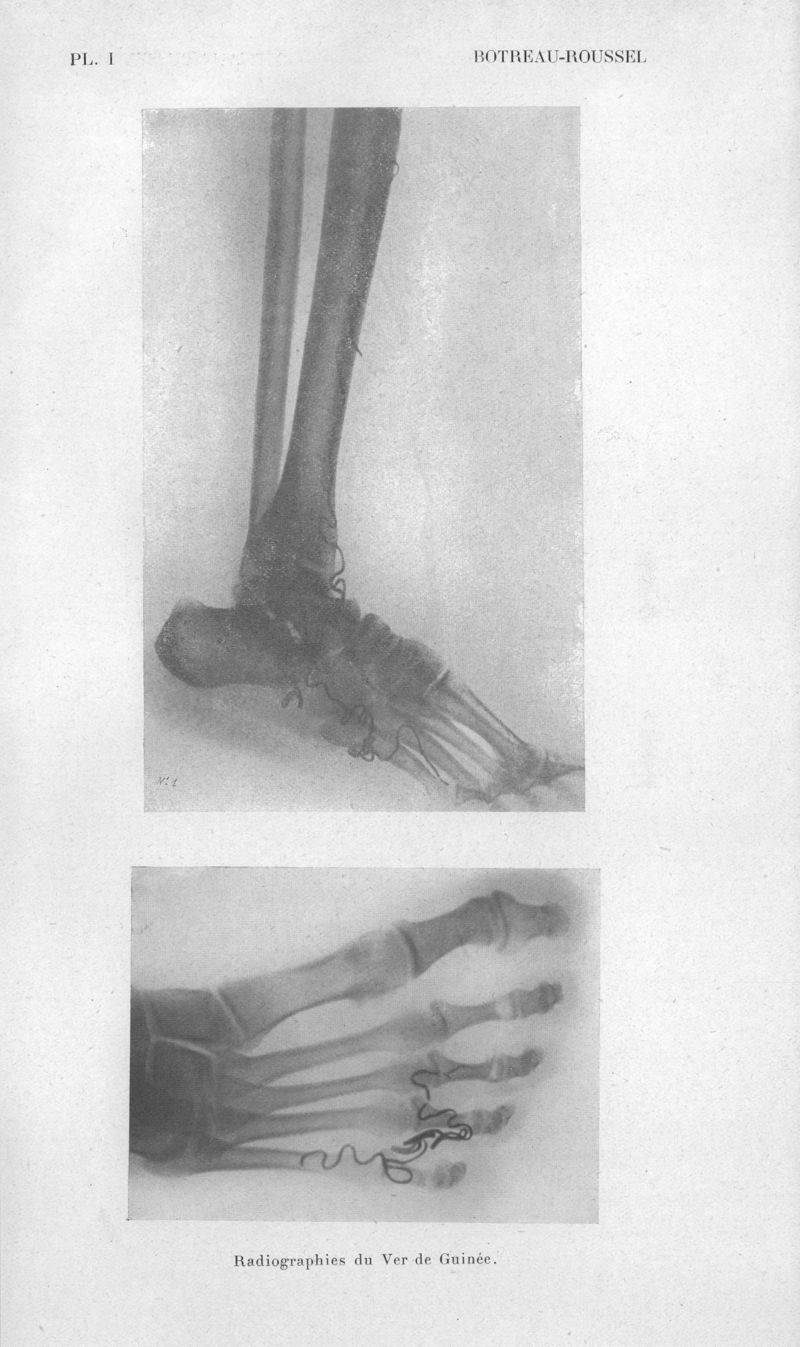

Bulletins de la Société de pathologie exotique et de ses filiales de l'Ouest africain et de Madagascar

1928, tome 21. - Paris : Masson, 1928.